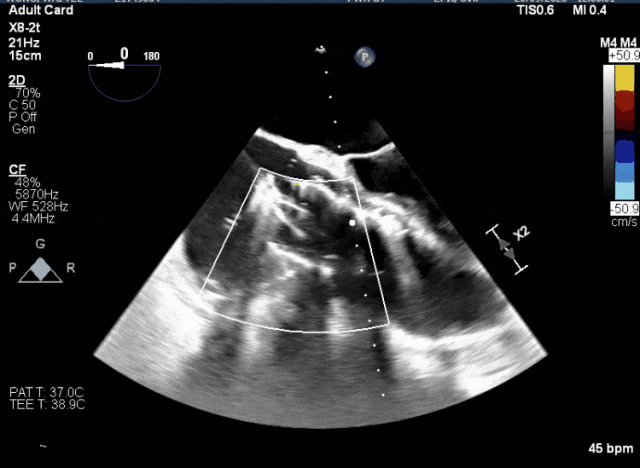

術中TEE成像困難,偽影干擾

術后DSA、超聲顯示人工瓣膜穩定性良好,瓣葉啟閉正常,無瓣周漏